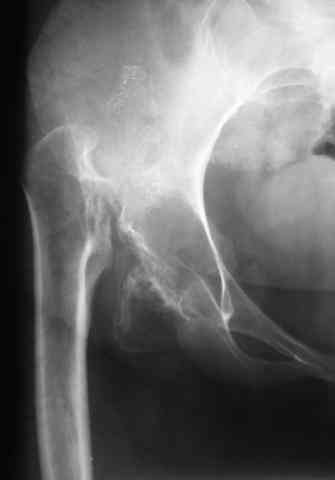

Уважаемые коллеги! В клинику обратилась больная 30 лет с жалобами на боль в области тазобедренных суставов (больше справа), ограничение движений в них.

Дисплазия была выявлена в 3-летнем возрасте, от операции родители тогда отказались. Около года назад при подъеме с кресла почувствовала резкую боль и хруст в правом бедре. С тех пор ходит только с ходунками. Выражены сгибательно-приводящие контрактуры. Справа - положительный симптом прилипшей пятки.

Мы планируем двустороннее тотальное бесцементное эндопротезирование. Первый этап - правый сустав. Чашку планируем имплантировать на свое анатомическое место, для чего резецируем часть бедренной кости. Смущают сильный остеопороз в области впадины и кривизна бедра... Ваши комментарии? -- С уважением, А. В. Вакуленко